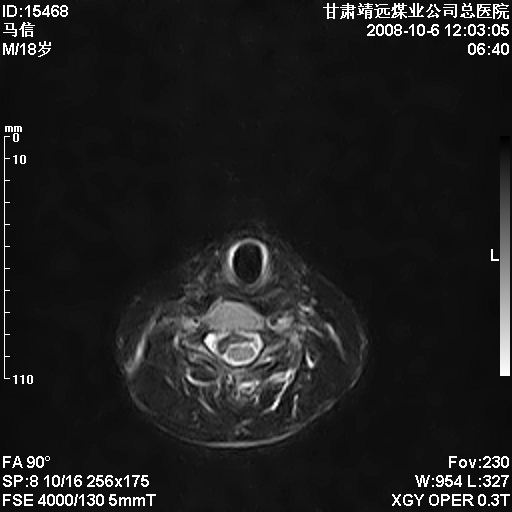

标题: MRI1827:颈椎内异常信号,是不是占位。

患者18岁,学生,在玩耍中受伤来检查,患者喜欢打篮球。颈椎内异常信号影,我们考虑占位,但是不像占位,又考虑硬膜囊的增厚,大家关建看颈椎椎管内的那个异常占位信号

腰椎的改变是不是正常发育的改变,还是打篮球的长期慢性损伤。

考虑 c3-4 c4-5 c5-6椎间盘突出,l3-4 l4-5 l5-s1椎间盘变性

颈椎建议做增强扫描;腰椎诸椎终板骨骺炎。

后纵韧带增厚,颈2/3、3/4、4/5、5/6椎间盘变性、突出;椎体有旋转,提示椎小关节有问题;腰椎间盘变性,许莫氏结节。